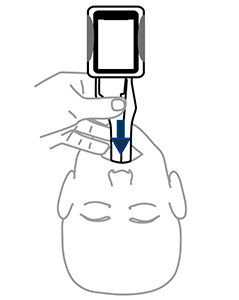

Slide midline around the tongue

Remove midline

Keep Midline